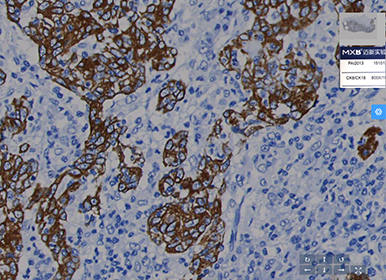

数字病理扫描仪通过将传统玻片转化为高分辨率的数字图像,实现了病理诊断从模拟到数字、从本地到云端、从人工到智能的跨越式发展。这项技术不仅让病理切片实现了永久性保存和即时性共享,更重要的是为远程诊断、多学科会诊、人工智能辅助分析等创新应用场景奠定了基础。医生可以在任何时间、任何地点通过专业软件对数字切片进行观察、标注和测量,而数字化的病理图像也为后续的定量分析和深度学习模型训练提供了高质量数据源。

当前,随着人工智能技术与病理诊断的深度融合,数字病理扫描仪正在从单纯的数据采集设备向智能诊断平台演进。通过将高质量的数字化病理图像与先进的人工智能算法相结合,可以实现对特定病变的自动识别、定量分析和风险预测,这不仅减轻了病理医生的工作负担,更提升了诊断的精准度和标准化水平。